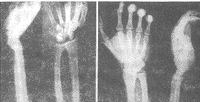

图2 王某,本奈氏骨折合并月骨脱位术前(左)后(右)X线片

中医正骨000257 王某,男,35岁。1997年9月24日用电泵给卸下的汽车轮胎充气时,轮胎爆裂,致钢彀弹起击伤右腕部,伤后2小时就诊。检查见右腕部肿胀明显,腕掌侧正中部压痛剧烈,腕部活动明显受限。第1掌骨基底部肿胀、压痛,可触及骨擦感及异常活动,各手指感觉正常。X线片示右腕月骨以掌侧缘为轴向前旋转90°凹面向前,位于头状骨前方。右第1掌骨基底部骨折,骨折线通过关节面,内侧有一三角形骨折块,无移位,其余基底部向背、外侧移位(图2左)。诊断为右本奈氏骨折合并月骨脱位。在臂丛神经阻滞麻醉下,先行月骨脱位手法复位。患者取坐位,患肩外展60°,屈肘90°,前臂旋前。两助手分别牵引患手及前臂,术者双手环抱腕部,双拇指按压腕背部,双中指末节叠加,指腹勾提腕横纹中点处皮下的月骨背侧缘,先下压腕部使腕关节极度背伸,然后双中指迅速向上提拉,使腕部掌屈,月骨复位。然后无菌操作,手法使第1掌骨头外展并向内前方推按其基底部,X线透视下自掌骨头外侧经皮穿入1枚直径1.5mm钢针,经髓内将基底部固定于大多角骨上。术后石膏外固定腕关节于掌屈30°位,第1掌骨外展位。拍片示复位良好。1周后改为腕关节中立位固定(图2右)。4周后去外固定并取出第1掌骨内固定钢针。开始行腕、指功能锻炼。随访1年,功能恢复良好,月骨无坏死。

讨论 该例病人腕部被高速运动的重物击伤,拇指首先受纵向传导暴力引起第1掌骨基底部骨折脱位,暴力继续作用使腕关节极度背伸,在桡骨远端与头状骨的挤压下使月骨向前脱位。月骨向前旋转90°,桡月背侧韧带断裂,桡月掌侧韧带完整,月骨血液供应未完全中断,提示预后较好。治疗以手法复位结合经皮穿针内固定,方法合理,达到预期目的。